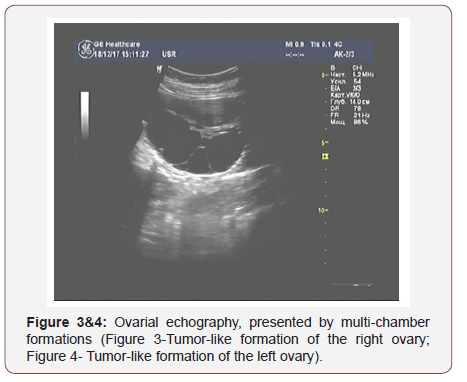

The results of ultrasound examination showed a single fetus in the uterus in the transverse position; in terms of its photometric parameters, the fetus fitted 31 weeks of gestation, the expectable estimated fetal weight was 1400 grams., a very thick placenta - up to 86mm (Figure 1) with medium echogenicity, multiple small anechoic structures (Figure 2), moderately expressed oligohydramnios (amniotic fluid index - 72mm) and a short neck uterus according to the results of cervicometry (20mm). Another feature is large, multichamber, an echogenic, bulky ovarian formations on both sides of the uterus (Figures 3&4). The size of the right ovary was 88 × 53 × 83mm, of the left one - 91 × 56 × 82mm. Hemodynamic disorders of the uteroplacental circulation were not detected.

Considering the data of ultrasonic examination of the fetoplacental complex and the revealed pathological changes, we noticed the signs of a trophoblastic disease (thick, swollen, cysticaltered placenta and echo graphic changes in the ovaries that indicate the presence of theca lutein cysts).